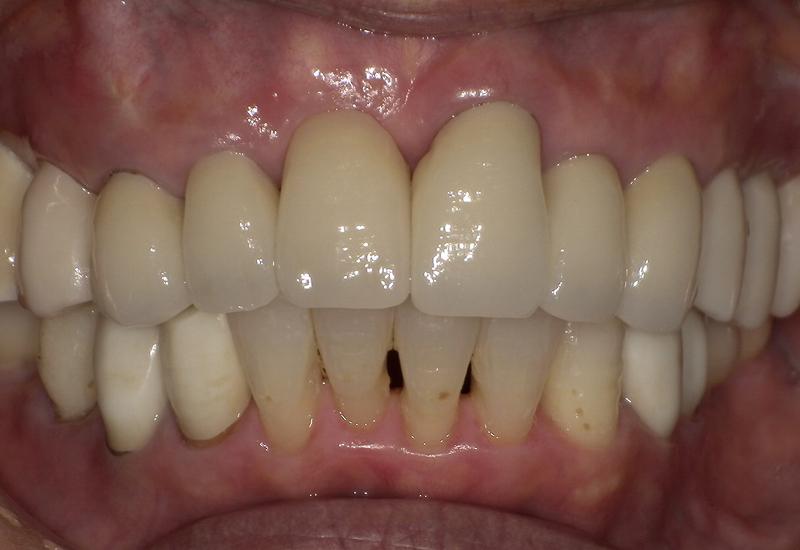

症例① シェイプメモリーアライナーによる下顎の前歯の矯正

治療期間 7ヶ月

治療時の年齢/性別 68歳 / 女性

かかった治療費 440,000円

治療方法 シェイプメモリーアライナー

注意点・詳細

• 根管治療をしてある歯はなるべく動かさない

• 下の前歯の歯の形を少しだけ小さく整えた